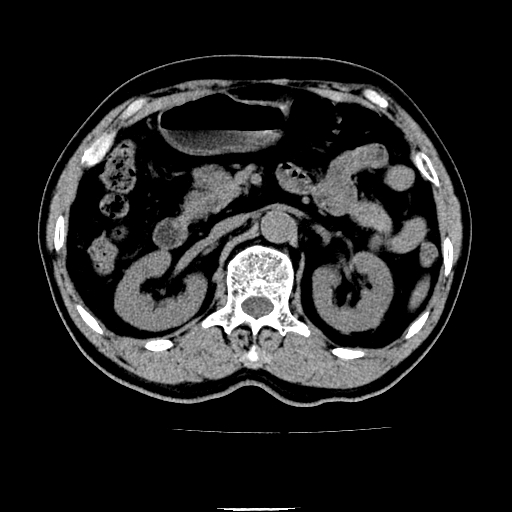

以下是引用chenqiong在2010-3-25 20:56:00的发言:[br]1、胆囊炎,胆囊息肉[br]2、肝内胆管及胆总管扩张,胆总管下端结石[br]3、十二指肠乳头旁憩室

以下是引用zxl51642在2010-3-26 10:47:00的发言:[br]胆囊炎,胆囊息肉,胆总管扩张,但未看到明显肿块,肝内胆管扩张不像恶性,炎性狭窄或阴性结石可能吧,建议mrcp,右肾小囊肿